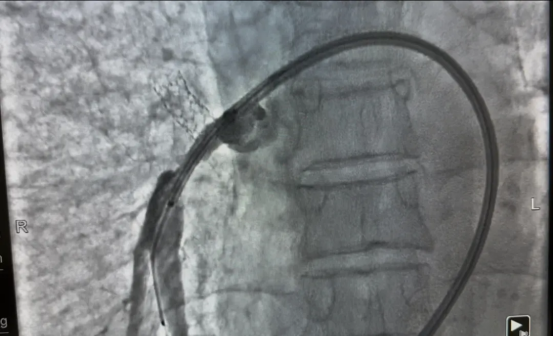

面对这一药物治疗效果有限、外科手术风险高的疾病,医疗团队制定了“微创、安全、有效” 的介入治疗方案。通过分次实施肺动脉成形术,逐步解除肺动脉狭窄,降低肺动脉压力。

疗效立竿见影。首次术后三天,张先生自觉气喘、胸闷明显缓解,阵发性干咳亦可耐受,肺动脉压降至66mmHg。完成三次手术后,他的肺动脉压已接近正常水平(40mmHg),日常活动完全不受限制,生活质量显著提升。